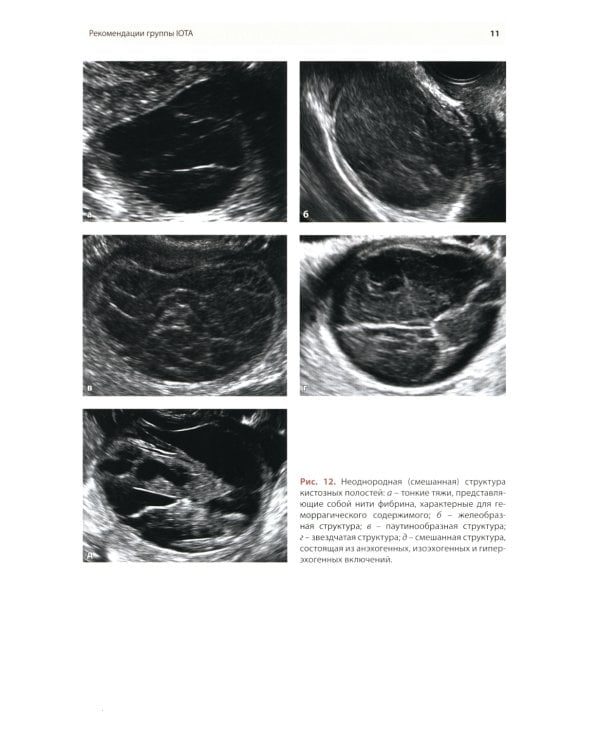

Методические рекомендации по стандартизации ультразвукового исследования с целью своевременной диагностики опухолевого процесса. Книга также включает вопросы дифференциальной диагностики физиологических изменений яичников, опухолевидных и опухолевых заболеваний и маршрутизации пациенток. Утверждено в качестве методических рекомендаций для проведения циклов первичной переподготовки врачей по ультразвуковой диагностике, тематического усовершенствования «Ультразвуковая диагностика в гинекологии», общего усовершенствования, ординаторов и аспирантов, проходящих обучение по направлению «Ультразвуковая диагностика, акушерство и гинекология».| Издательство | МЕДпресс-информ |